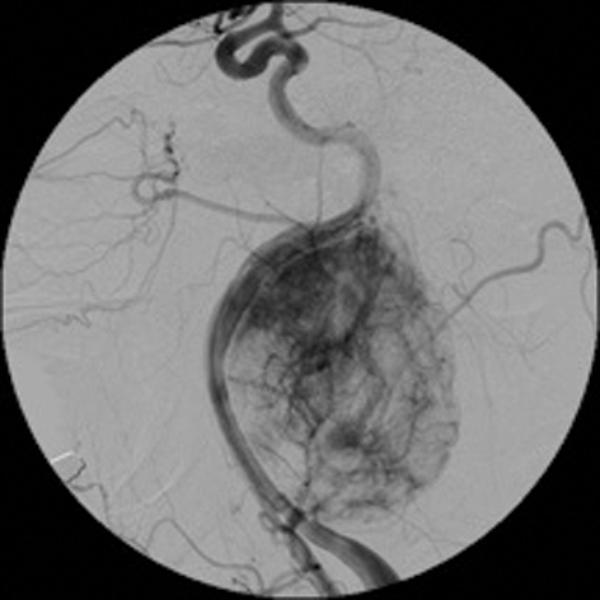

Arterio-venous (AV) fistulae are abnormal connections between arteries and veins which can be congenital, spontaneous or traumatic. Treatment of AV fistulae of head and neck also falls within the remit of interventional neuroradiology. These lesions are often difficult to treat surgically because of multiplicity of feeders and difficulty in access etc.

Endovascular treatment of AV fistulas involves preservation of the normal vasculature and occluding both the distal and proximal vessels of the fistula.

Detachable balloons, particles and / or sclerosants, and stents are used in the endovascular treatment of these lesions. (Figure 3 shows a case of a traumatic external carotid-jugular AV fistula treated by coil embolisation).

Figure 3: ECA- jugular fistula before and after embolisation.